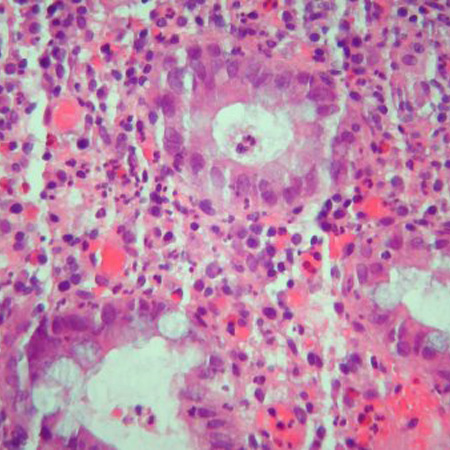

[Figure caption and citation for the preceding image starts]: Cryptitis and crypt abscess with morphological distortion of the crypts accompanied by inflammation and abundant lymphatic and plasma cellsCourtesy of Drs Wissam Bleibel, Bishal Mainali, Chandrashekhar Thukral, and Mark A. Peppercorn; used with permission [Citation ends].